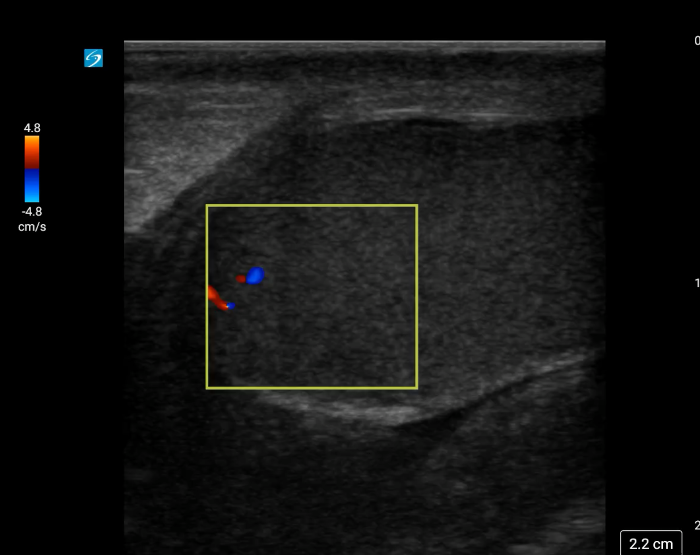

[Torsion - image 2.pngImage 2. Twisted spermatic cord (“corkscrew sign”) concerning for testicular torsion.

In your first image (Image 1), you realize there is no flow with color Doppler. Additionally, you find a torsed cord complex (Image 2), also known as the “corkscrew sign.” You consult Urology who is busy in the operating room with another case. You decide to perform a manual detorsion due to your concern for testicular atrophy and risk of infertility. Using the open book technique, you get relief of pain and return of vertical positioning of the testicle after two rotations. On your repeat testicular POCUS with color Doppler you obtain these images (Images 3 and 4), which demonstrate venous and arterial flow throughout the testicle. The cord is now untwisted and appears linear in orientation.

In the presence of testicular torsion, the spermatic cord will have a twisted appearance at the superior testicle. Twisting of the spermatic cord, commonly known as corkscrew sign, may be visible at the superior testis. (Image 8)

Video 7. Color Doppler demonstrating a twisted spermatic cord.

Torsion - image 8.pngImage 8. The corkscrew sign can be appreciated when using color Doppler.